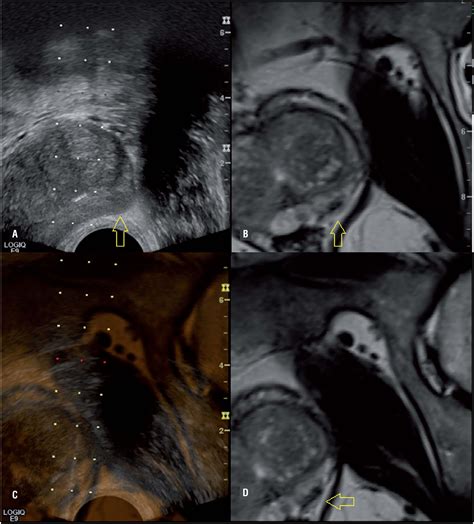

• Fusion imaging: Fusion imaging combines MRI images with ultrasound images to provide a more accurate and detailed view of the prostate. This can be particularly useful for guiding prostate biopsies and planning treatment.